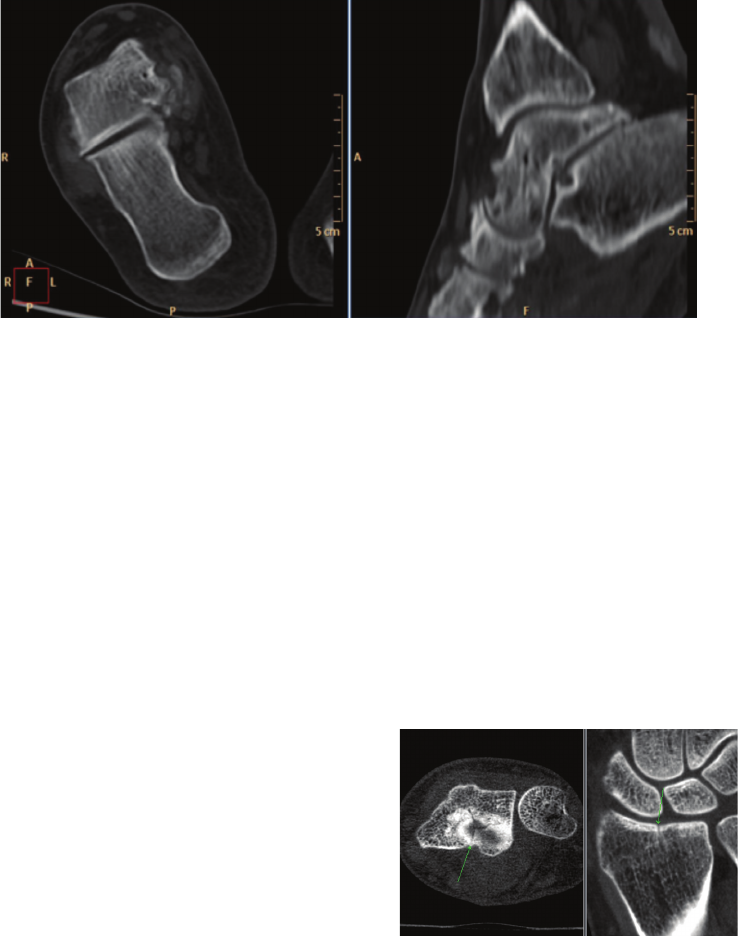

Figure 7 CT images of the foot acquired on a conventional spiral CT system. In-plane (transverse)

pixel size is 0.75 mm × 0.75 mm and slice thickness is 3 mm. Note the degradation in observed

spatial resolution in the sagittal view (right image) compared to the transverse view (left image)

due to the anisotropic voxel size.

Figure 8 High-resolution, low-dose CT images of

a 32-year-old female acquired with BrightView XCT

(CTDIVOL = 3.75 mGy). Patient had chronic right

wrist pain after distal radius fracture ve months

prior to SPECT/CT study. CT images reveal a star-like,

residual, not yet fused fracture of the distal articular

surface of the radius.

Clinical data courtesy of Cantonal Hospital Lucerne,

Lucerne, Switzerland

any angle. So unlike conventional spiral CT images

which typically have poorer resolution in the sagittal

and coronal views due to the thicker slices compared

to the in-plane transverse pixel size (see Figure 7),

XCT images viewed in the sagittal or coronal planes

(or other oblique angles) have the same resolution

as the transverse images because of the isotropic voxels.